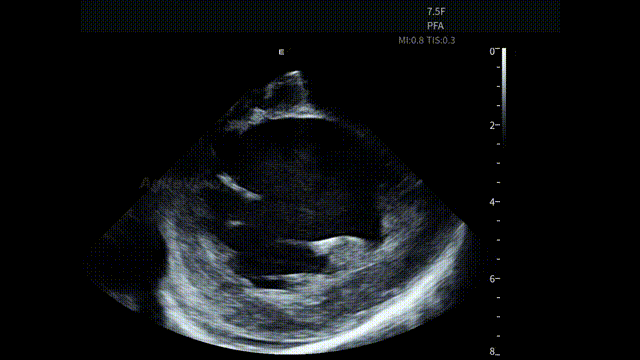

手术开始后,蒋晨阳教授将 AgileView™ 7.5Fr ICE 导管置入右心房,首先通过 HomeView 视角建立心腔整体参照,并对左心耳血栓及心包情况进行系统性评估。术前影像显示心包存在少量积液,为后续操作提供了重要的基线参考。

HomeView

左心耳血栓筛查

术前心包筛查-有少量积液

术后心包筛查-积液无变化